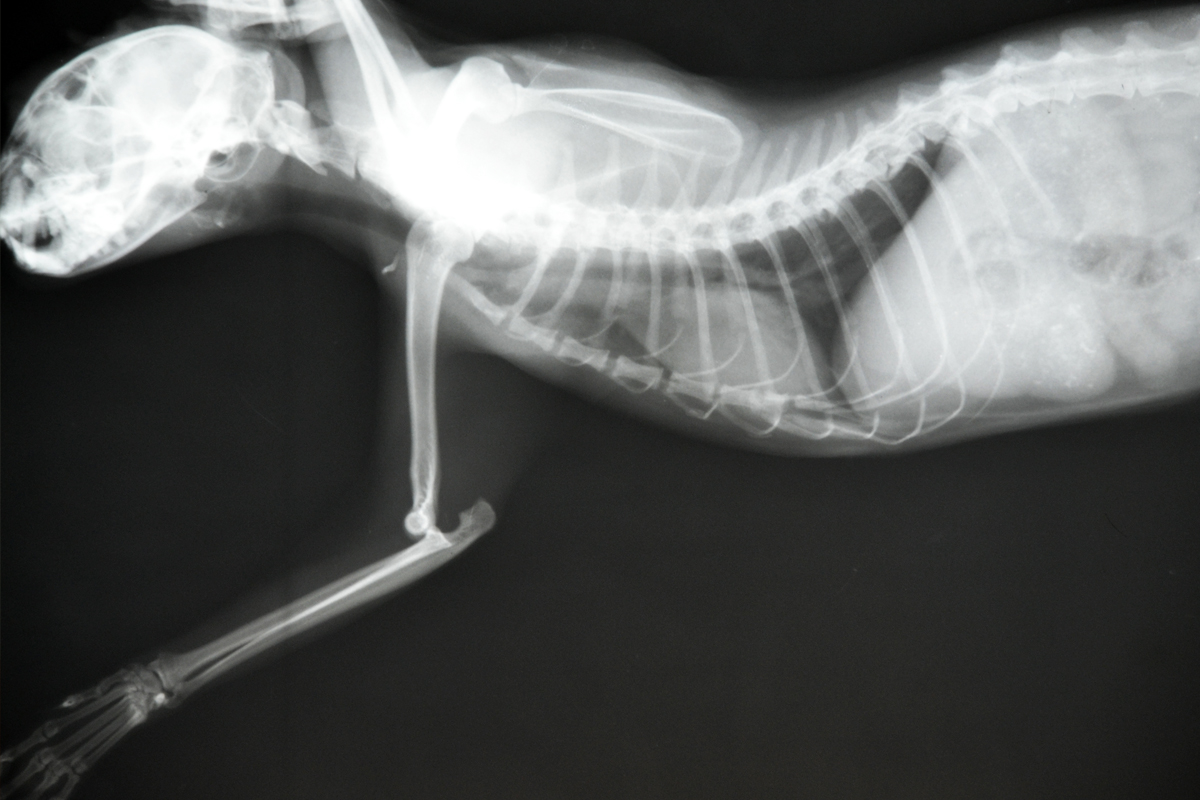

Рентгеновские снимки перелома лапы у кота: диагностика и лечение